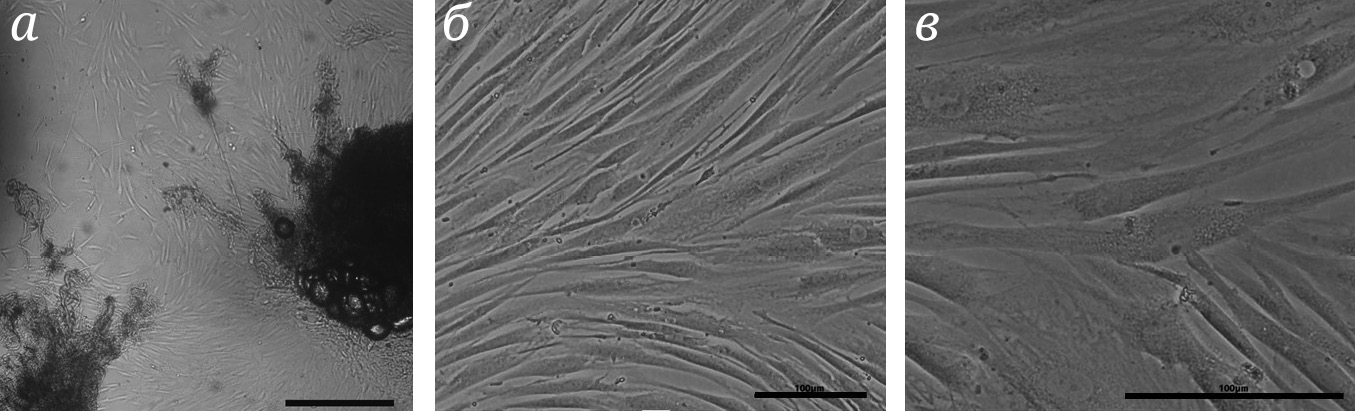

Биоптат кожи был получен от женщины 36 лет с подтверждённым диагнозом БХ. В результате генетического исследования пациента в последовательности гена обнаружено 47 повторов кодона CAG. Из фрагмента биоптата спустя две недели культивирования была получена первичная культура дермальных фибробластов (рис. 1, а).

Рис. 1. Общий вид полученной линии фибробластов. а – Прижизненная микрофотография фрагмента биоптата и первичных фибробластов. Световая микроскопия. Масштаб 200 мкм. б и в – Прижизненные микрофотографии линии дермальных фибробластов на 7-м пассаже с увеличением 10× и 20× соответственно. Световая микроскопия. Масштаб 100 мкм

В результате серии пассажей была получена клеточная линия, представленная гомогенной популяцией дермальных фибробластов и названная HDDF (Huntington Disease Dermal Fibroblasts) (рис. 1, б и в). В полученной клеточной линии не было выявлено контаминации бактериями, грибами и микоплазмой. STR-анализ подтвердил уникальность данной популяции и отсутствие кросс-контаминации другими клеточными линиями (не публикуется, информация будет размещена в паспорте клеточной линии). Также был проведён эксперимент по определению числа CAG-повторов в гене HTT полученной клеточной линии, выявивший количество повторов, равное 46 ± 2. Полученные фибробласты имеют характерную для данного типа клеток веретенообразную форму (рис. 1, в). Клетки активно пролиферируют в процессе длительного культивирования, сохраняют высокую жизнеспособность после криоконсервации, которая составляет не менее 80%.